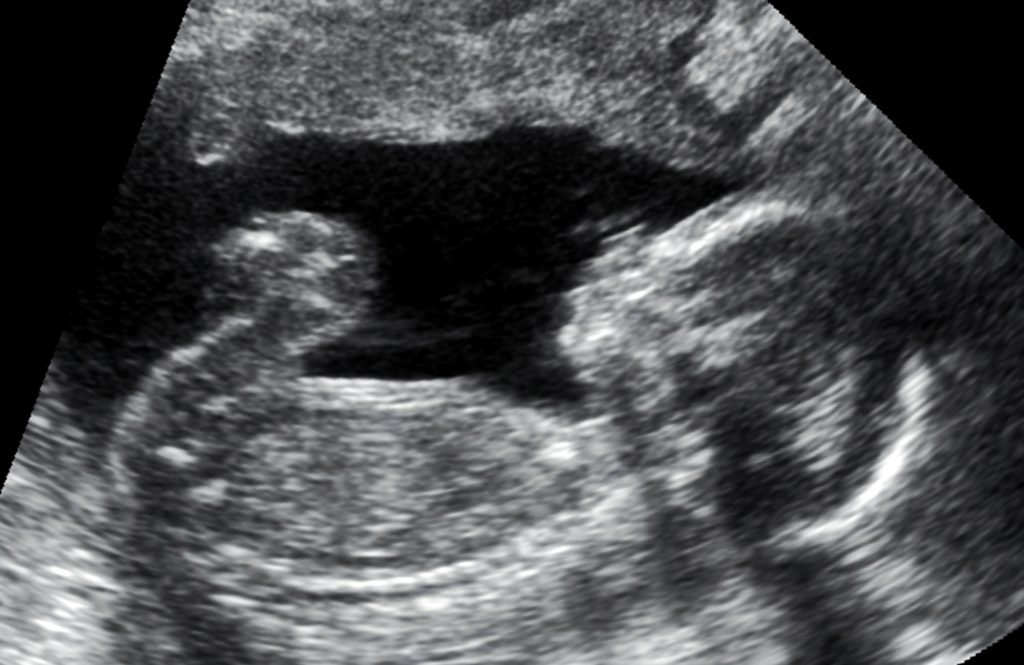

De acordo com a decisão, a mulher fez ultrassonografias em diversas unidades médicas, que apontaram a síndrome, caracterizada por um cordão umbilical rudimentar ou ausente, amplo defeito de fechamento da parede abdominal anterior fetal e cifo-escoliose acentuada, podendo vir acompanhada de alterações nos membros que geralmente causam imobilidade no feto.